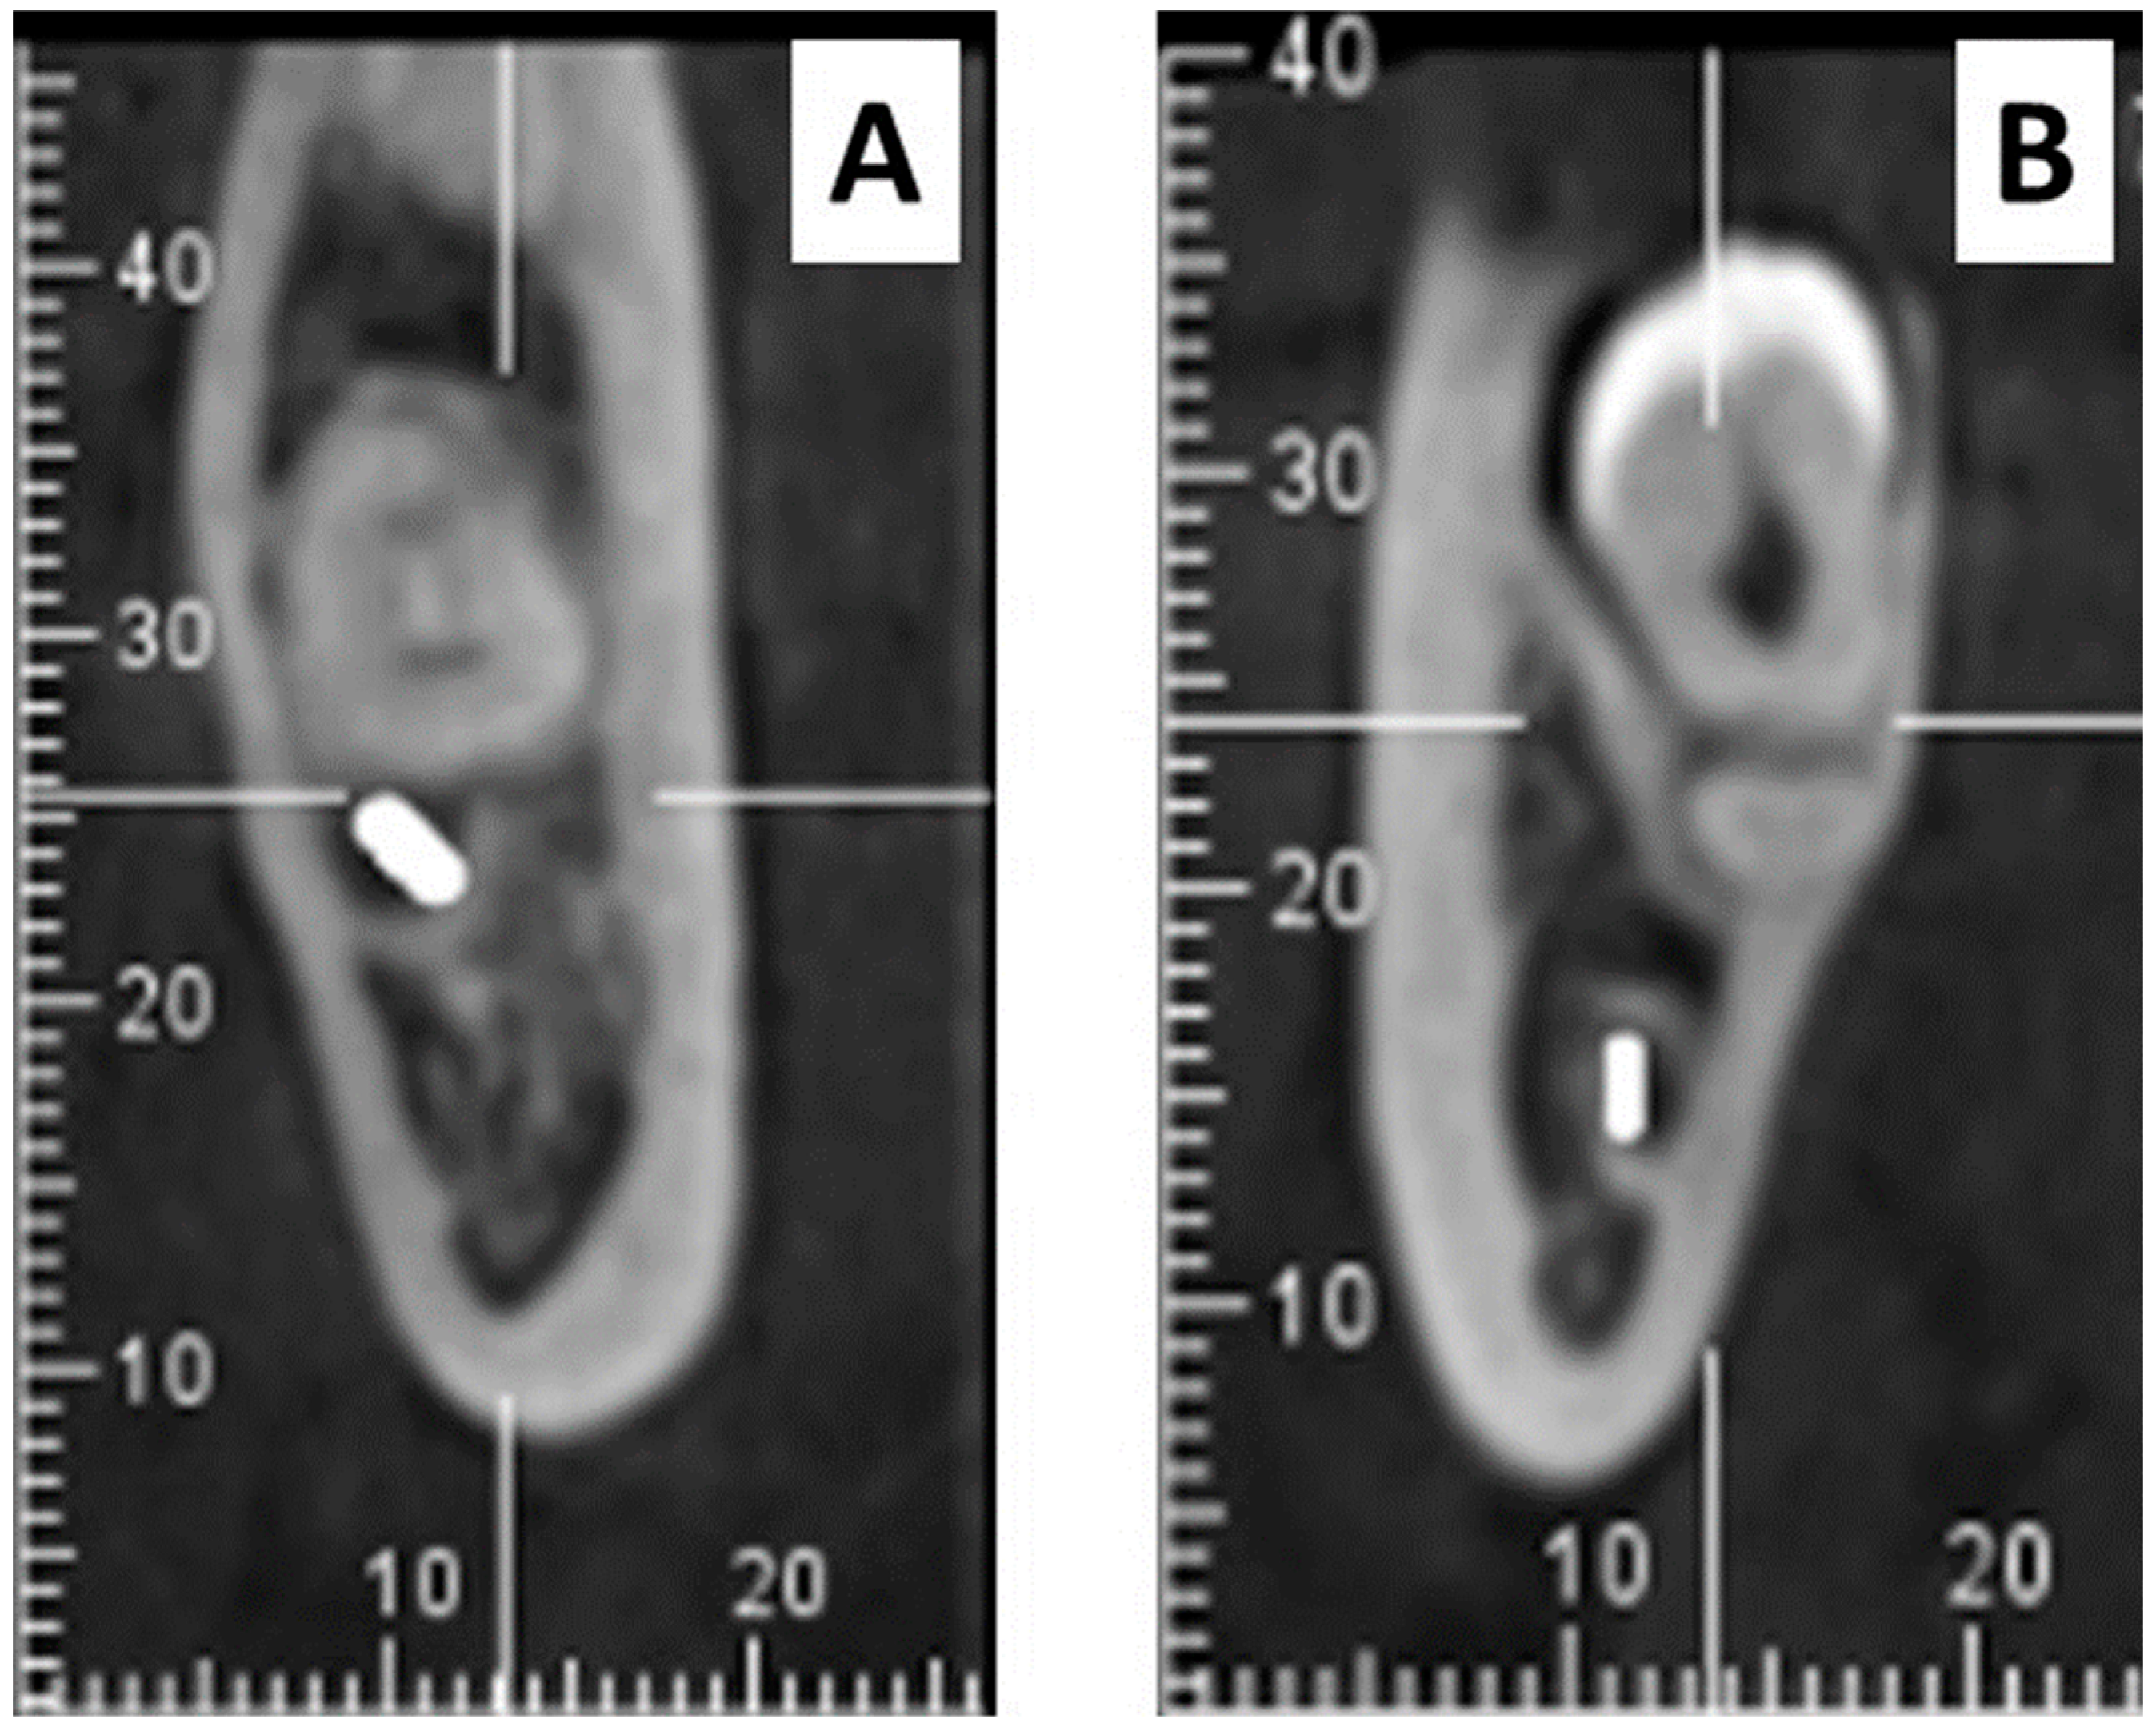

- a)

- Radiolucency at the root

- b)

- Narrowing of the root

- c)

- Radiolucency and bifurcation at the root apex

- d)

- Discontinuity of the mandibular canal cortex

- e)

- Narrowing of the mandibular canal

- f)

- Deviation of the root

- g)

- Deviation of the mandibular canal

- h)

- Superimposition of the root and the mandibular canal (overlapping)